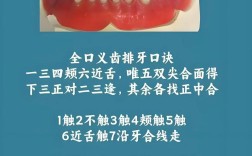

- 常见形式: 可摘局部义齿(部分活动假牙)、全口义齿(全口假牙)。